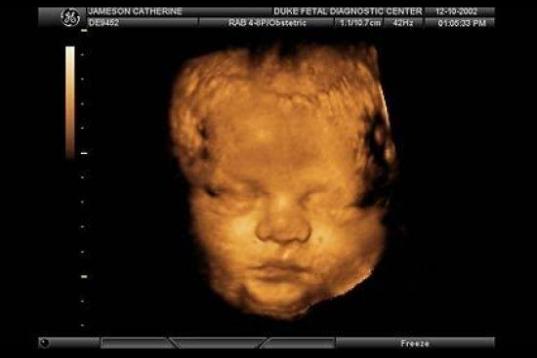

En esta galería puedes ver en fotos como es el desarrollo de un feto de semana en semana:

Desarrollo del feto, en fotos